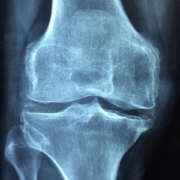

In today’s fast-paced world, many of us find ourselves tethered to our desks for hours on end, often at the expense of our musculoskeletal (MSK) health.Whether you’re navigating the challenges of remote work or enduring long hours in a customary office, managing MSK pain is crucial for maintaining productivity and overall well-being.In this listicle, we present five essential tips designed to help you alleviate discomfort and enhance your work experience. From ergonomic adjustments to mindful movement techniques,you’ll discover practical strategies that can seamlessly integrate into your daily routine. Say goodbye to nagging aches and hello to a more comfortable work environment as you learn how to take control of your MSK health.